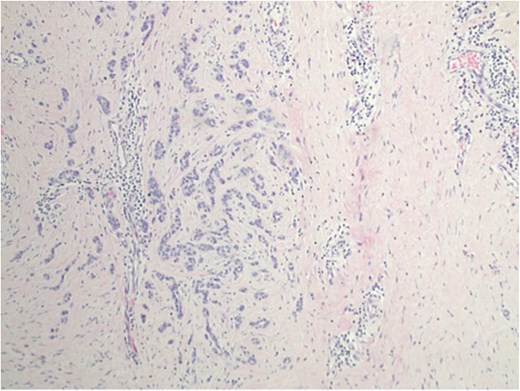

A complete left central partial mastectomy with sentinel lymph node biopsy was performed. The lumpectomy specimen revealed IDC, infiltrating into the deep dermis of the overlying nipple (Fig. 2). Pathological stage was IA T1cN0M0 IDC. Adjuvant chemotherapy was not indicated because of a low Oncotype DX score. She completed adjuvant left whole-breast radiation but declined adjuvant endocrine therapy.

Invasive ductal carcinoma infiltrating into the deep dermis of the overlaying nipple.